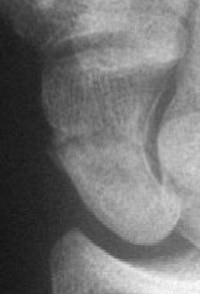

Case 5. Another,same bidirectional technique. Here, I ran the second screw too close to the first, and may have flattened the leading threads - not

ideal. The preop status: